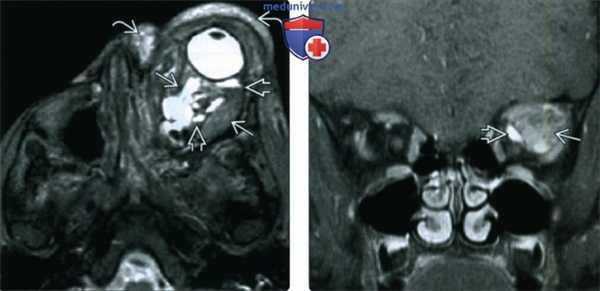

(Слева) При Т2-взвешенной МРТ в аксиальной проекции определяется массивная лимфатическая мальформация сложной формы, вызывающая экзофтальм. Жидкое содержимое, скопившееся в результате неоднократных кровоизлияний, дает вариабельный сигнал и формирует уровни раздела. Также виден еще один, пресептальный, компонент образования.

(Справа) При МРТ Т1ВИ FS с КУ в левой глазнице определяется крупное образование сложной формы, содержащее по большей части неконтрастируемый субстрат, дающий вариабельный Т1-сигнал. Контрастируемая структура с медиальной стороны представляет собой венозный компонента, вероятно, мелкий варикозный узел.